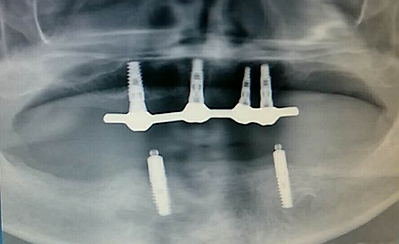

毛國(guó)斌種植病例——群討論分享